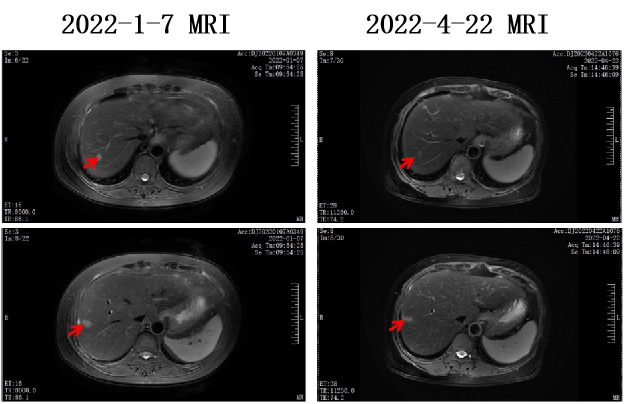

2022-1-8至2022-5-20 共行6周期 贝伐珠单抗+伊立替康+奥沙利铂+卡培他滨方案化疗。

术后5周期化疗后复查疗效为SD。

2022-6-22 开始行贝伐珠单抗+卡培他滨维持治疗。